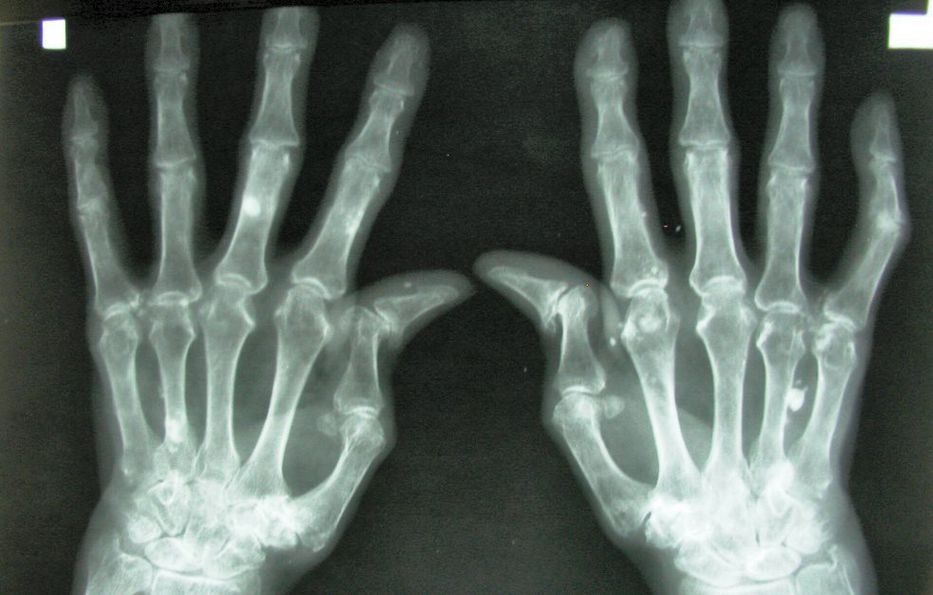

Los análisis de sangre de la proteína C reactiva (PCR) y de la tasa de sedimentación eritrocítica (TSE) pueden ayudar a los médicos a evaluar la gravedad de la inflamación en los pacientes de artritis reumatoide, apuntaron los investigadores.

Los estudios anteriores han sugerido que las mujeres obesas podrían normalmente tener unos niveles más altos de PCR y TSE. Los autores del estudio decidieron observar este tema más de cerca.

Un índice de masa corporal (IMC, un cálculo de la grasa corporal según el peso y la estatura) más alto se asoció con una PCR más alta en las mujeres con artritis reumatoide y en las mujeres en la población general, sobre todo en las mujeres con una obesidad grave. También hubo una asociación modesta entre la obesidad y la TSE.

Al contrario, en los hombres con artritis reumatoide, un IMC más bajo se asoció con una mayor PCR y TSE.